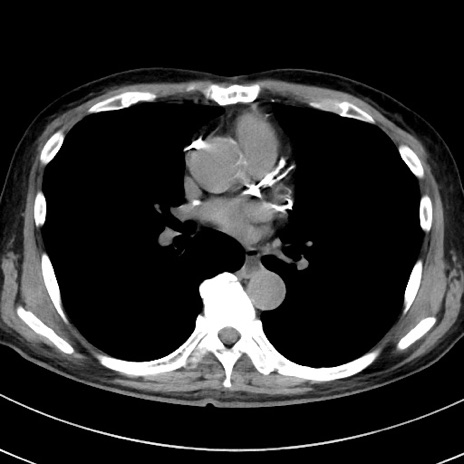

症例38(横断像)

【症例】70歳代 男性

【主訴】腹痛・嘔吐

【現病歴】昨晩より、嘔吐・腹痛あり。今朝になっても嘔吐あり。来院。

【既往歴】心臓バイパス手術、開腹胆摘、腸閉塞

【身体所見】BP 107/71mmHg、HR 116/min、腹部:平坦、軟、下腹部に軽度圧痛あり。反跳痛なし。

【データ】WBC 15100、CRP 0.32